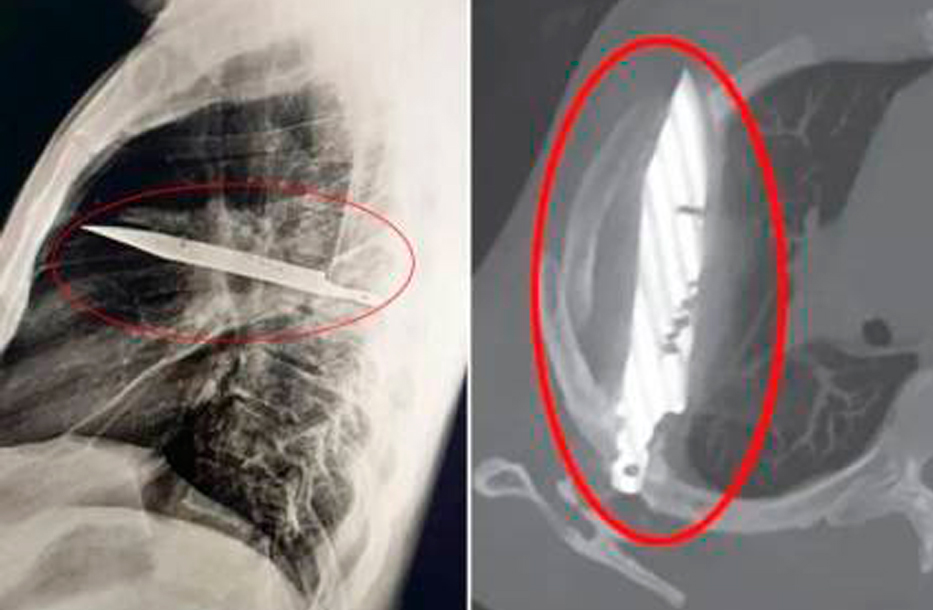

Los médicos lograron suturar las heridas en aquel entonces, y había vivido una vida prácticamente sin incidentes, hasta que su pezón comenzó a supurar pus. Incapaces de determinar la causa de la infección, los médicos solicitaron una radiografía y se sorprendieron al ver una hoja de cuchillo gigante alojada en su pecho.

La radiografía lateral inicial mostró un objeto metálico retenido en la parte media del tórax, con opacificación circundante que probablemente representa un hematoma loculado en resolución o crónico, o fibrosis postraumática, una secuela de la puñalada del paciente, escribieron los médicos en su estudio de caso.

De alguna manera, la hoja del cuchillo, que había entrado por la escápula derecha, logró milagrosamente eludir cualquier órgano importante. En el momento del altercado del hombre, hace ocho años, el hospital donde fue atendido no tenía medios para realizar una investigación radiológica, y como no refirió dolor después de que sus heridas cicatrizaron, nadie se molestó en investigar más a fondo.